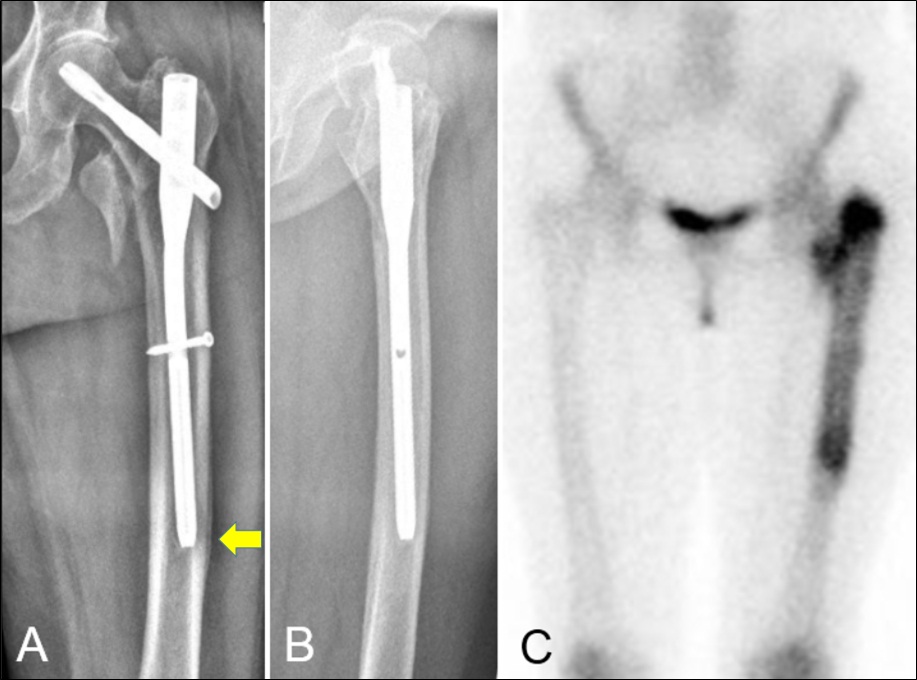

Penetración de la cortical anterolateral en fracturas de fémur proximal tratadas con clavos endomedulares cortos Reporte de dos casos. [Penetration of anterior-lateral cortex in proximal femur fractures treated with short intramedullary nails Report of two cases].

7. Ostrum RF, Levy MS. Penetration of the distal femoral anterior cortex during intramedullary nailing for subtrochanteric fractures: a report of three cases. J Orthop Trauma 2005;19:656-60.

9. Egol KA, Chang EY, Cvitkovic J, Kummer FJ, Koval KJ. Mismatch of current intramedullary nails with the anterior bow of the femur. J Orthop Trauma 2004;18:410-5.